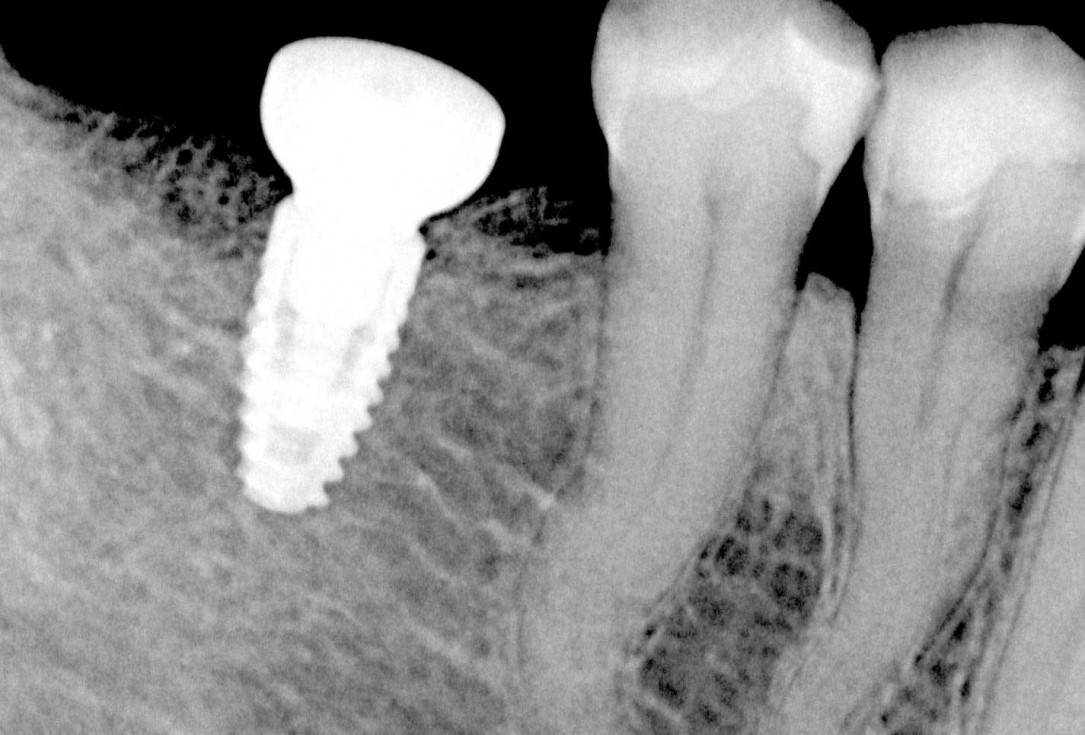

Initial x-ray, ten years post implantationem alio loco, large peri-implant bone loss

Initial x-ray showing bone loss around implants placed 5 years ago in another dental clinic